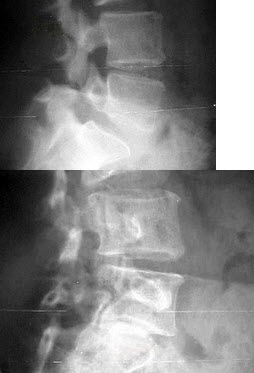

28、单项选择题

男,17岁,下肢畸形,有皮肤色素沉着,性早熟等,结合图像,最可能的诊断是()

A.非骨化性纤维瘤

B.骨巨细胞瘤

C.骨纤维结构不良

D.内生软骨瘤

E.畸形性骨炎